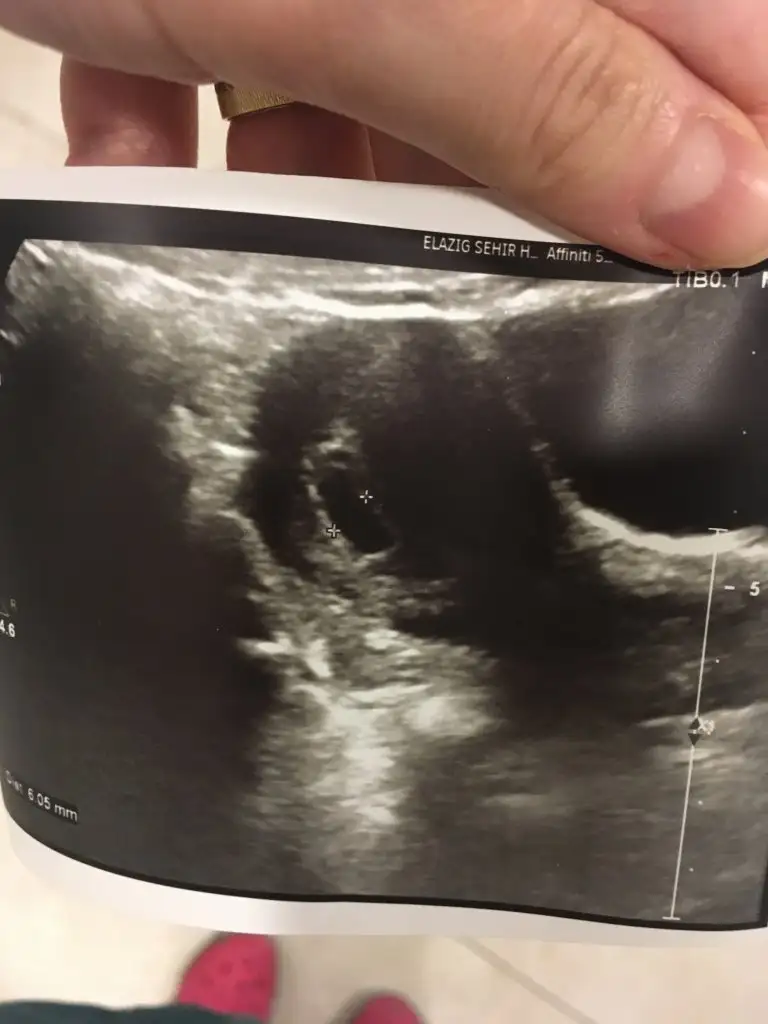

Merhaba kızlar simdi doktordan geliyoruz özelde yeni bir doktora basladık ilk randevuydu kalp atışını göremeyiz muhtemelen demisti basta doktor ama gördük cok şükür insallah bundan sonrasıda sağlıkla ilerlerDarısı tüm bekleyen annelerin başına insallah❣

Canım foto varmı bebeğin benim dikkatimi bişey cekti kese içinde bişey var inşallah bebektir üstte çizgi gibiDarısı başınıza insallah sizde görün tez zamanda 6+5 bugun

Canım foto varmı bebeğin benim dikkatimi bişey cekti kese içinde bişey var inşallah bebektir üstte çizgi gibi

seninki baya büyük benim üstte çizgi gibi bişey var şimdi dikkatimi cekti sizde gördünüzmü benim keseyivar canım bu hizalı olan bebek yanındaki yuvarlak görünümde yolk kesesi. Benimkinde de bebek düz gözüküyor.